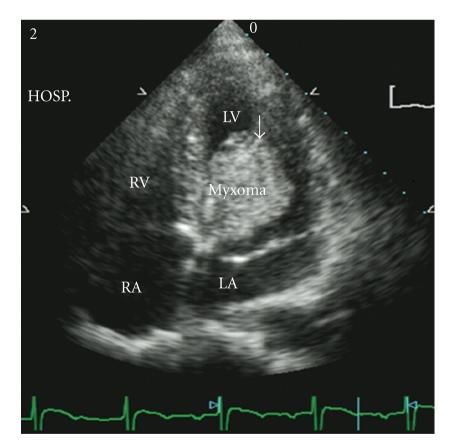

Background. Although thrombolytic therapy has been shown to be beneficial to stroke patients, the effectiveness of intravenous thrombolysis in ischemic stroke patients with ventricle myxoma is unknown. Case Description. A 22-year-old woman with left hemiplegia was sent to the emergency department at a teaching hospital. The magnetic resonance angiography showed occlusion of the right middle cerebral artery, and the echocardiography showed a mass in the left ventricle. Intravenous recombined tissue plasminogen activator (rt-PA) was administrated, and the postthrombolysis transcranial Doppler exam showed that her right middle cerebral artery was circulative. The patient's condition improved gradually, and no complication was observed up to 16 months of follow-up. Conclusion. Intravenous rt-PA is a reasonable treatment for stroke patients with ventricle myxoma.

背景。尽管溶栓治疗已被证明对中风患者有益,但静脉溶栓治疗在患有心室黏液瘤的缺血性中风患者中的有效性尚不清楚。病例描述。一名22岁左侧偏瘫女性被送往一家教学医院的急诊科。磁共振血管造影显示右大脑中动脉闭塞,超声心动图显示左心室有肿物。给予静脉注射重组组织型纤溶酶原激活剂(rt-PA),溶栓后经颅多普勒检查显示其右大脑中动脉有血流。患者病情逐渐改善,随访16个月未观察到并发症。结论。静脉注射rt-PA是患有心室黏液瘤的中风患者的合理治疗方法。